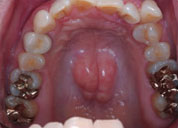

- PROTUBERANCE

- 骨隆起

- 上顎(口蓋隆起)

- 下顎